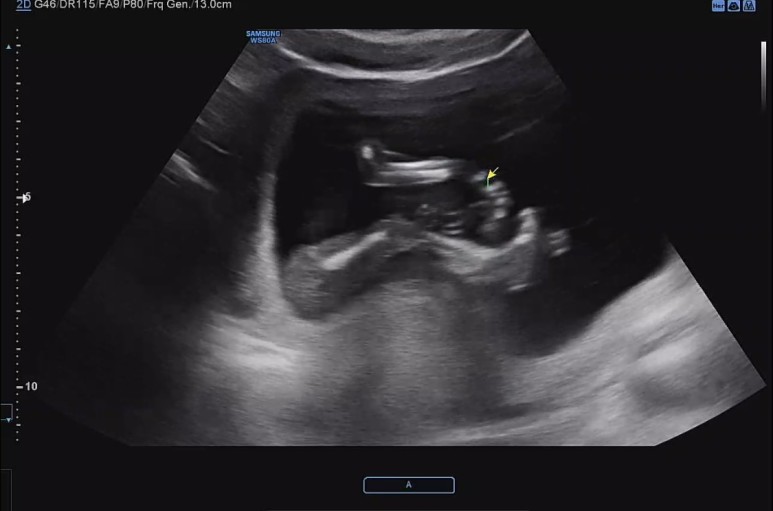

꿀잠이 오늘은 똑바로 앉아있기.

4주가 지나니 이제 척추뼈가 하나하나 다 보이고 머리도 훌쩍 커진게 눈에 보인다.

쭉 뻗고 앉아있는 귀여운 ㅋㅋ 다리 ㅋㅋ

요기는 팔꿈치.

손을 머리쪽으로 올리고 있다.

이제 초음파 영상 구분하는 고수가 되어서 어디가 어딘지 척척.

콧대도 확인하고.

벌써 머리통이랑 콧날이 예쁜것 같아 내새꾸.

초음파 선생님이 엉덩이 사이를 열심히 들여다 보셨지만, 탯줄이 교묘하게 가리고 있어서 도저히 성별을 가늠할 수 없다고 하셨다. 그런데 내 느낌엔 슬쩍 슬쩍 지나가는 화면에 다리 사이에 아무것도 보이지 않는게 자꾸 포착되어서 딸인것 같은 느낌적인 느낌을 느꼈다..!